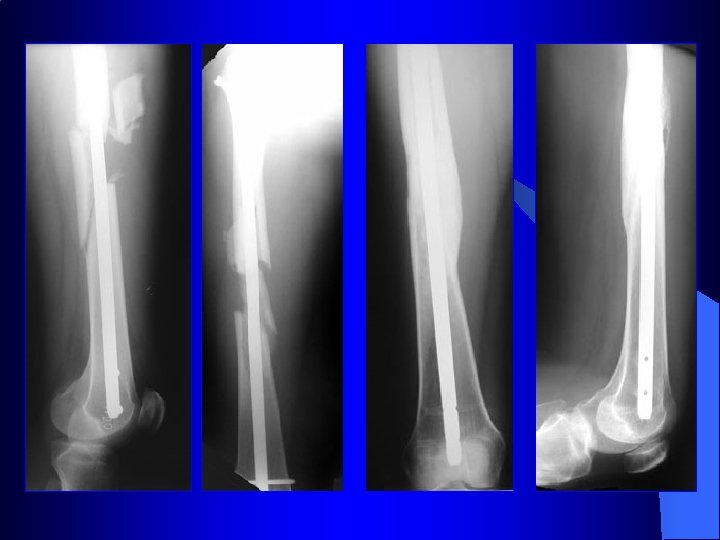

Contention Chirurgicale (Ostéosynthèse) A foyer fermé • Abord à distance du foyer de fracture • Pas de contact avec la fracture • Réduction de la fracture par manœuvre • Introduction d’une tige externe sous contrôle radio guide dans les 2 fragments • Introduction des alésoires de calibres croissants • Introduction du clou • Il est possible de verrouiller le clou dans l’os par des vis transversales

Clou pour tibia Courbure adaptée Clou creux

ü Avantages : l l l Pas de déperiostage des fragments Pas d'évacuation de l'hématome périfracturaire Mobilisation précoce des articulations Appui précoce Bonne qualité du cal obtenu Moins de risque de fracture itérative à l'ablation (après 18 mois)

ü Inconvénients : l l l Réduction non anatomique Pas de compression possible Trouble de rotation

Classiquement l Principalement dans les fractures Diaphysaire

Enclouage du tibia à foyer fermé Clou simple Clou à ailettes Clou verrouillé par vis